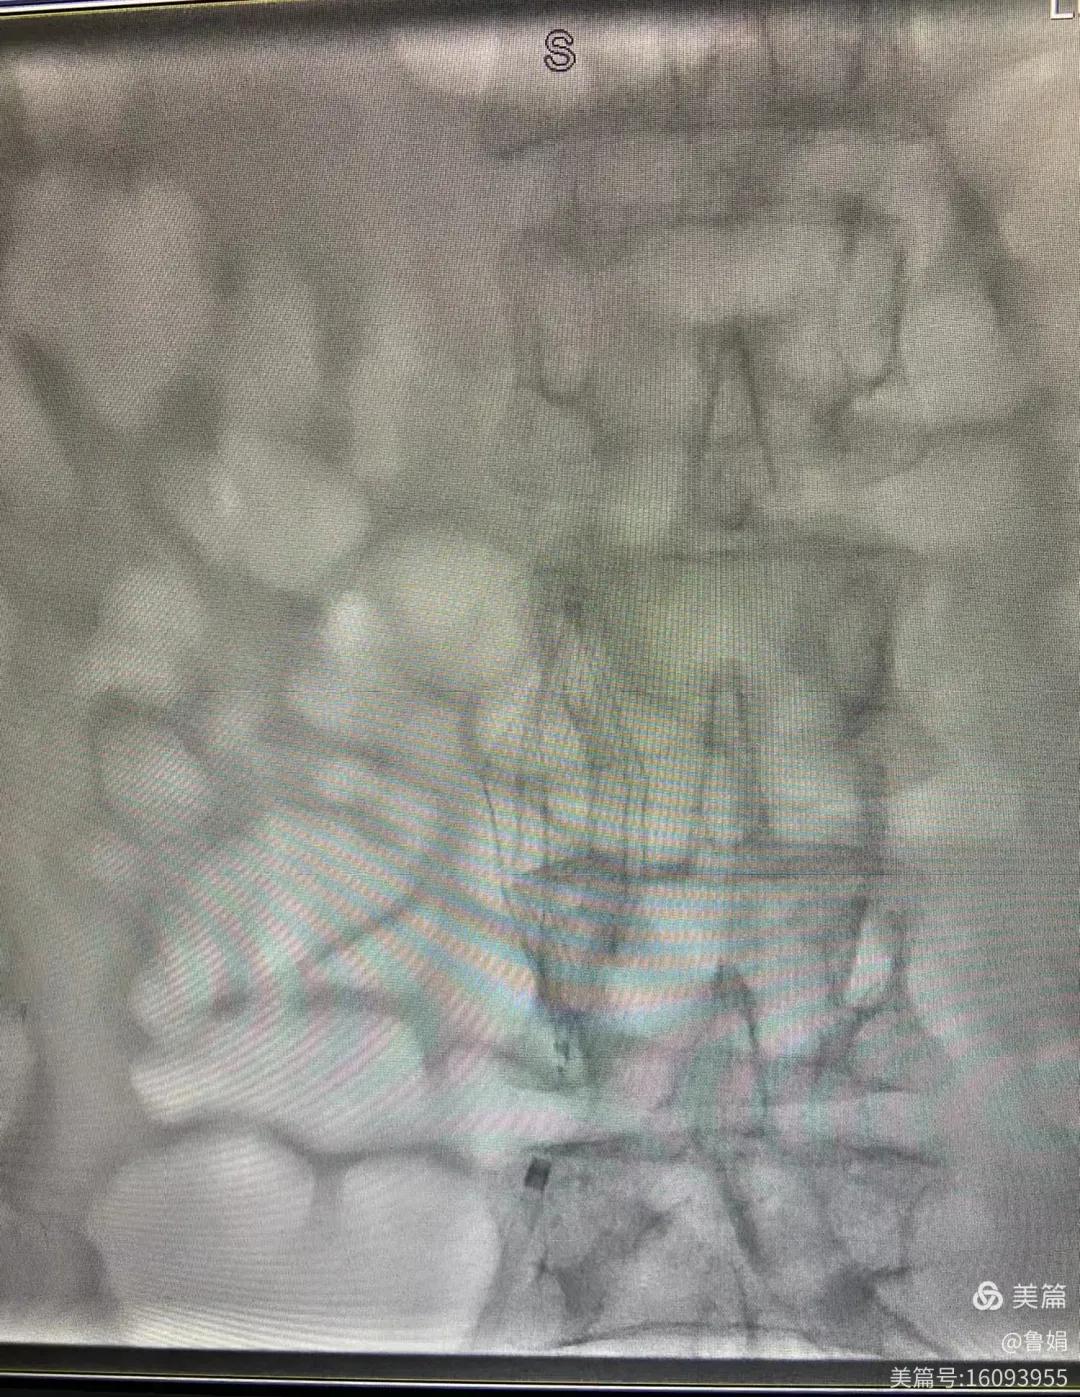

圖片術(shù)后濾器順利植入

經(jīng)認(rèn)真查看患者病例,探討患者病情及術(shù)中潛在風(fēng)險因素,多科會診后急診為患者開展介入手術(shù),術(shù)中周創(chuàng)業(yè)副主任、孫亞中副主任中醫(yī)師二人通力合作,手術(shù)順利,病人術(shù)中出血少,生命體征平穩(wěn),現(xiàn)在腦二科病房繼續(xù)對癥治療。(介入中心:魯娟)